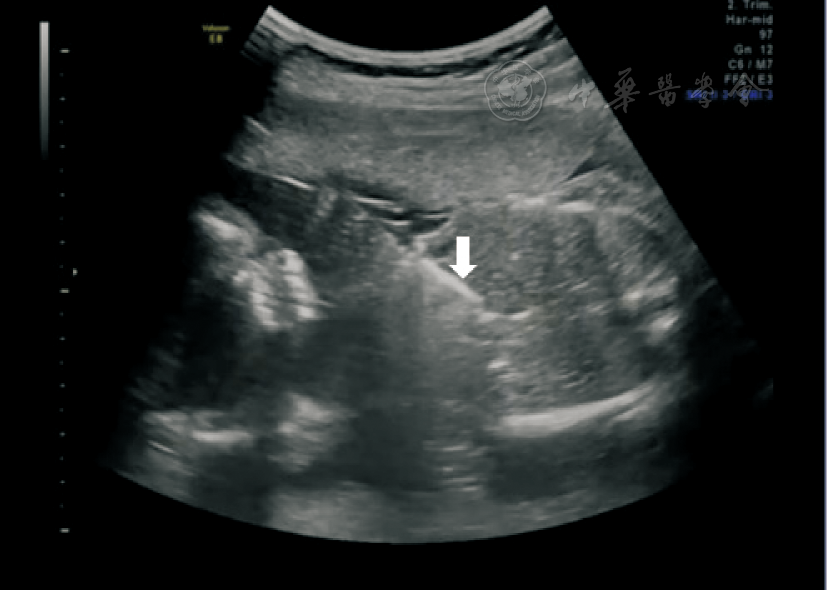

图1 病例2患者超声引导下射频消融减胎术图片。箭头所指为射频消融针,射频消融位点为供血胎脐带插入腹内侧段